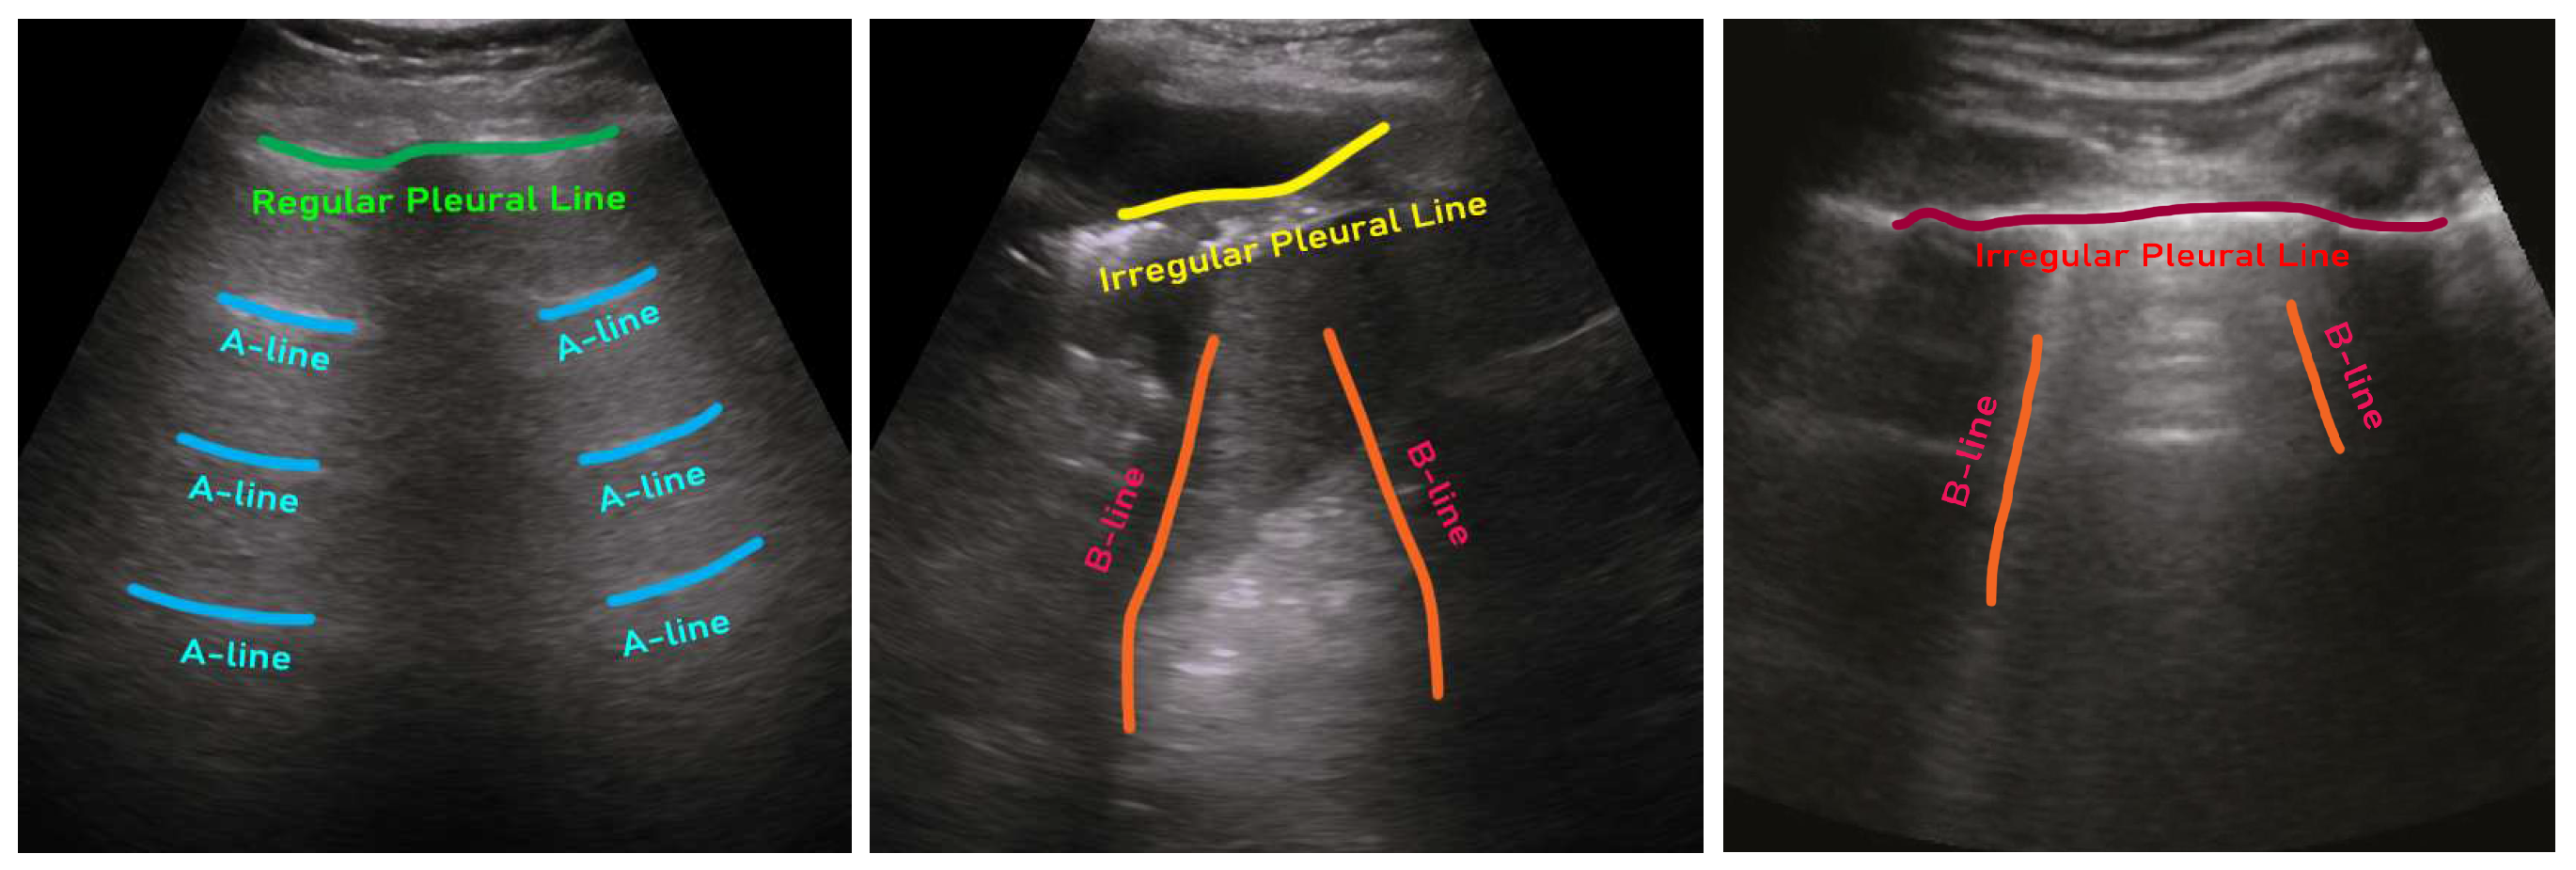

- ICLUS-DB: Soldati et al. [24] published an internationally standardized acquisition protocol and four-level scoring schemes for lung ultrasound (LUS) in March 2020. This dataset contains 277 ultrasound videos (consisting of 58,924 frames) of 17 confirmed COVID-19, 4 suspected COVID-19, and 14 healthy subjects. These data were collected at various clinical centers in Italy using various ultrasound scanners by either linear or convex probes. To evaluate the progress of pathology, this data consortium defined a four-level scoring system ranging from 0 to 3. The presence of continuous pleural-line and horizontal A-lines indicates a healthy lung with a score 0. Score 1 is tagged for initial abnormality when alterations in the pleural line appear. Score 2 is more severe than 1 and is associated with small consolidations in the lung. Score 3 is the most severe grade, which is associated with the presence of a larger hyperechogenic area below the pleural surface (i.e., white lung).